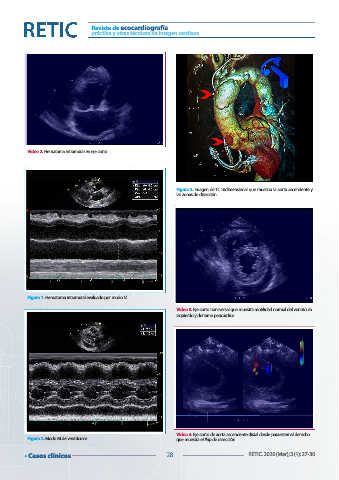

Vídeo 2. Hematoma intramural en eje corto

Figura 3. Imagen de TC tridimensional que muestra la aorta ascendente y

las zonas de disección

Figura 1. Hematoma intramural evaluado por modo M

Vídeo 3. Eje corto transversal que muestra motilidad normal del ventrículo

izquierdo y derrame pericárdico

Vídeo 4. Eje corto de aorta ascendente distal desde paraesternal derecho

Figura 2. Modo M de ventrículos que muestra el flap de disección